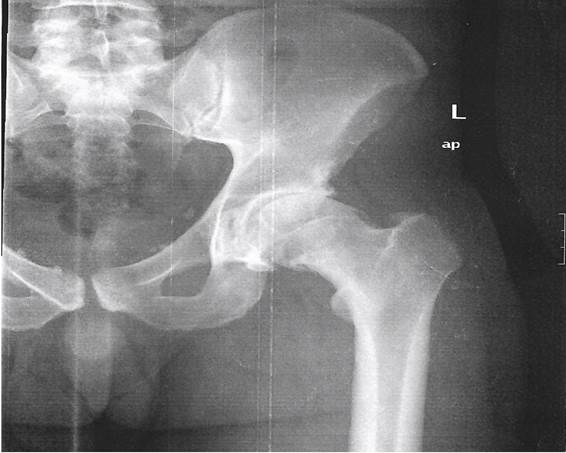

En la exploración física se evidencia dolor inguinal a la movilización activa y pasiva, acentuándose en rotación interna y aducción de la cadera; disminución del arco de movilidad en flexión y rotación externa. Signo de Drehmann y test impigement positivos. Se decide pautar antiinflamatorios y solicitar radiografía simple de cadera antero-posterior, en la que se evidencia esclerosis subcondral, osteofitos, “giba lateral” (“pistolgrip": deformidad en mango de pistola) con pinzamiento femoroacetabular, deformidad de cabeza y rotura del labrum acetabular (Figura 1). Dados los hallazgos, se decide derivar a los pacientes a Reumatología donde, tras la valoración, deciden solicitar RM de caderas, que confirma los cambios degenerativos junto con necrosis avascular grado III de la cabeza femoral izquierda, signos diagnósticos de un síndrome femoroacetabular tipo CAM (Figura 2). Actualmente ambos pacientes presentan una limitación para la deambulación con antiinflamatorios pautados de forma crónica.